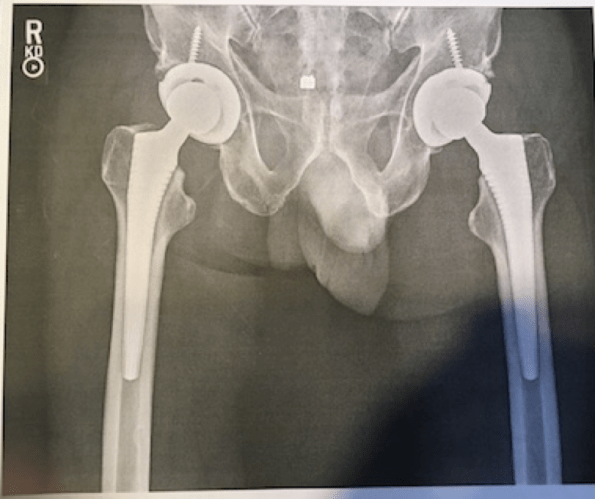

3. Ex-Hippie’s Hips 2018